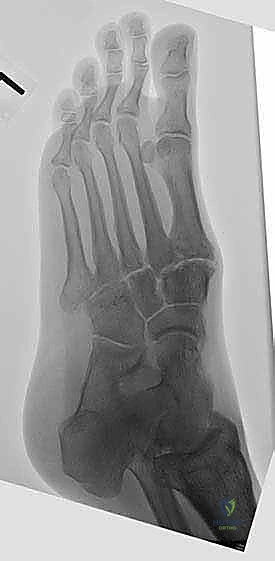

لفهم أهمية جراحة تثبيت مفصل منتصف القدم، يجب أولاً أن نفهم التشريح الفريد لهذه المنطقة. يتكون منتصف القدم (Midfoot) من مجموعة من العظام الصغيرة التي تتشابك معاً لتشكيل قوس القدم (Foot Arch). هذه العظام تشمل:

* العظم الزورقي (Navicular): يقع في الجانب الداخلي للقدم.

* العظم النردي (Cuboid): يقع في الجانب الخارجي.

* العظام الإسفينية الثلاثة (Cuneiform bones): تقع في المنتصف وتربط بين العظم الزورقي وعظام مشط القدم.

تعمل هذه العظام معاً كـ "ممتص للصدمات" أثناء المشي والجري. المفاصل التي تربط هذه العظام (مثل مفصل تارصو-ميتاتارسال أو مفصل ليزفرانك Lisfranc joint) هي مفاصل ذات حركة محدودة جداً، ولكنها حيوية لاستقرار القدم. عندما تتآكل الغضاريف التي تغطي نهايات هذه العظام، تبدأ العظام بالاحتكاك ببعضها البعض، مما يولد ألماً مبرحاً ويؤدي إلى انهيار قوس القدم.